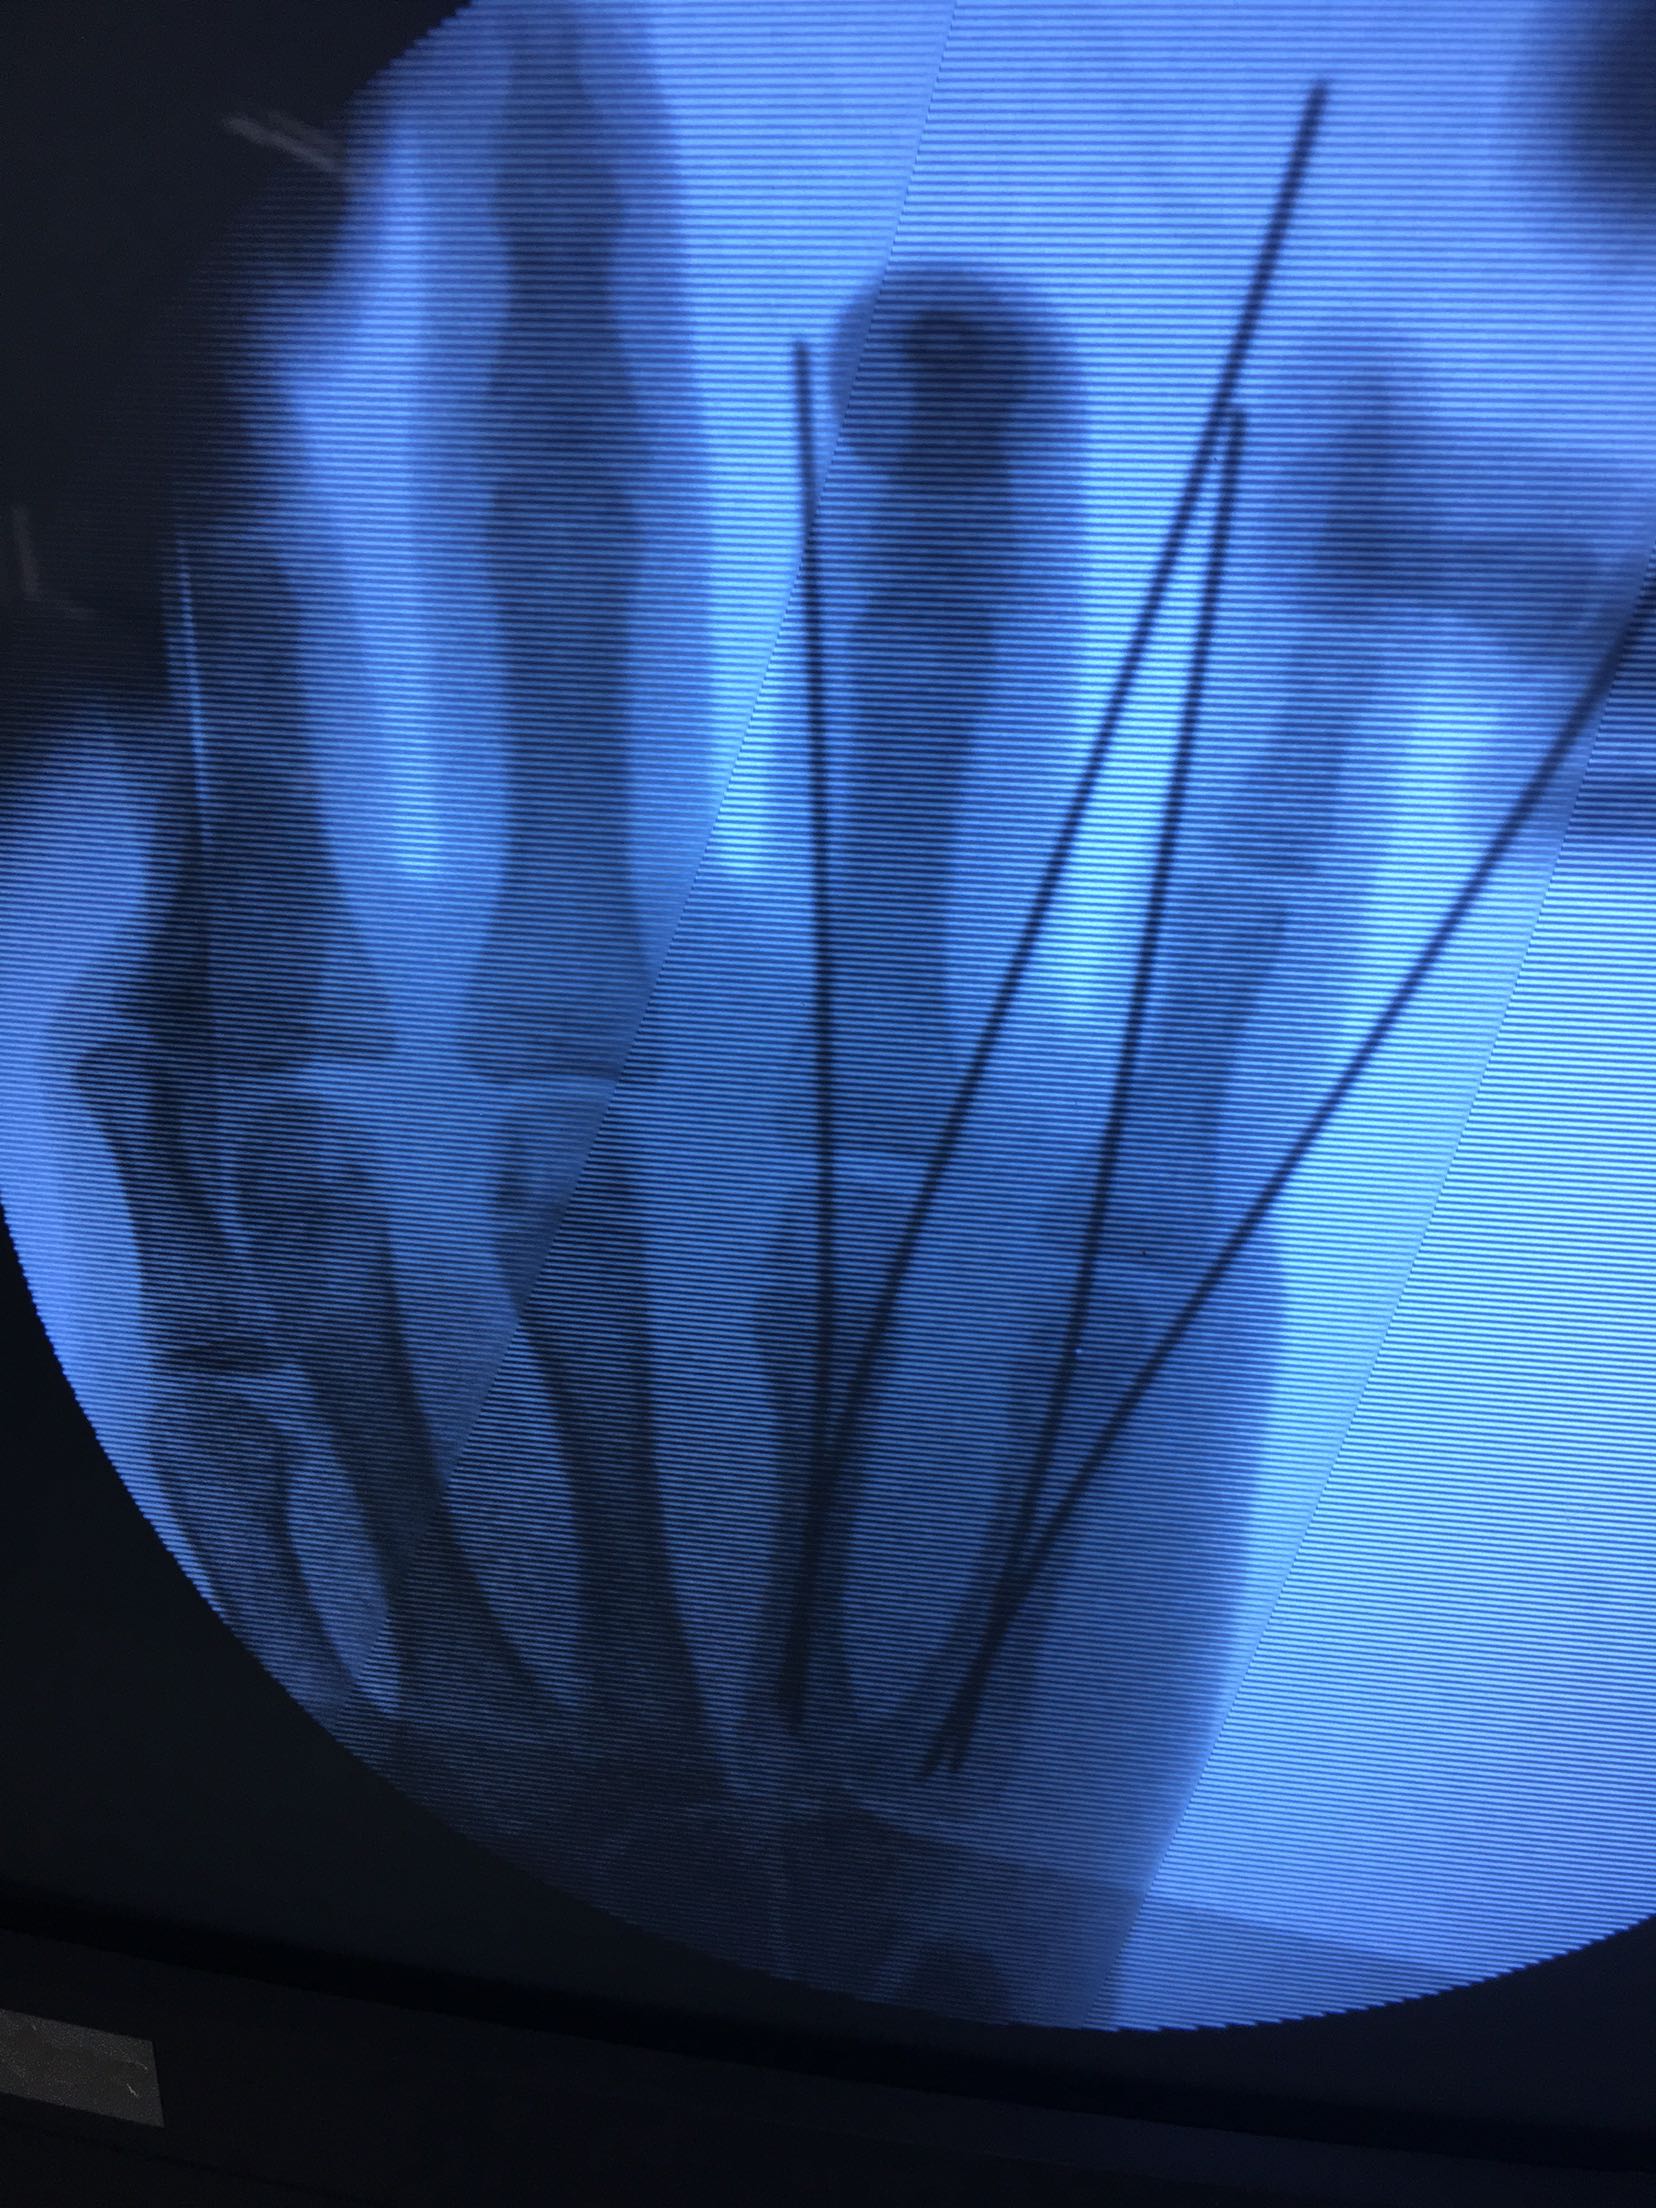

完善检查,在臂丛麻醉下行闭合复位内固定术,术后抗炎,消肿止痛等对症处理,右手石膏托制动。